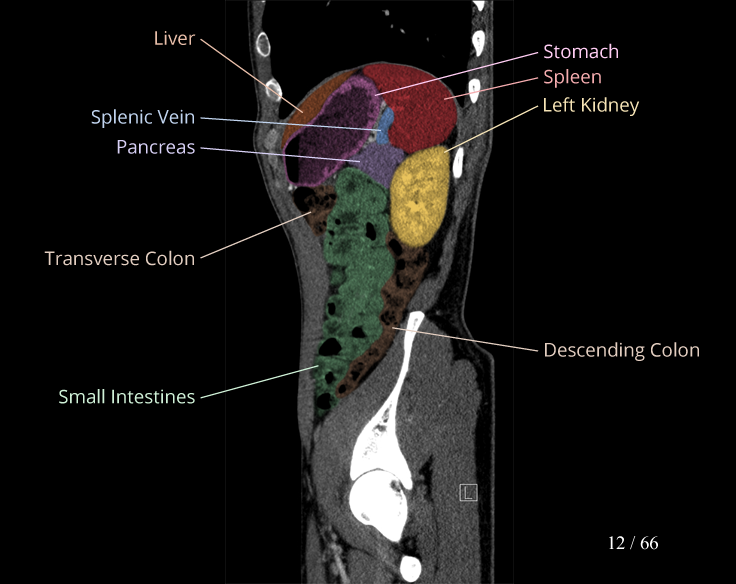

Body

Covers abdominal CT anatomy.